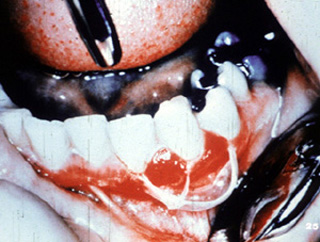

También pueden afectarse otras áreas del mucosa oral. Este señor presenta ulceraciones dolorosas de los mucosa bucal y labio. El examen clínico reveló  úlceras superficiales irregularmente formadas.

En otra vista, las lesiones están presentes en la mucosa yugal y la encía edentula.

En el interrogatorio el paciente manifiesta incomodidad ocular. Hay eritema e irritación de la conjuntiva de los ojos. Ésta es la consecuencia más seria de la enfermedad porque estas lesiones en la  conjuntiva pueden dejar  cicatriz y con el tiempo pueden producir ceguera.

La biopsia fue realizada y el diagnóstico es pénfigo benigno de las membranas mucosas.